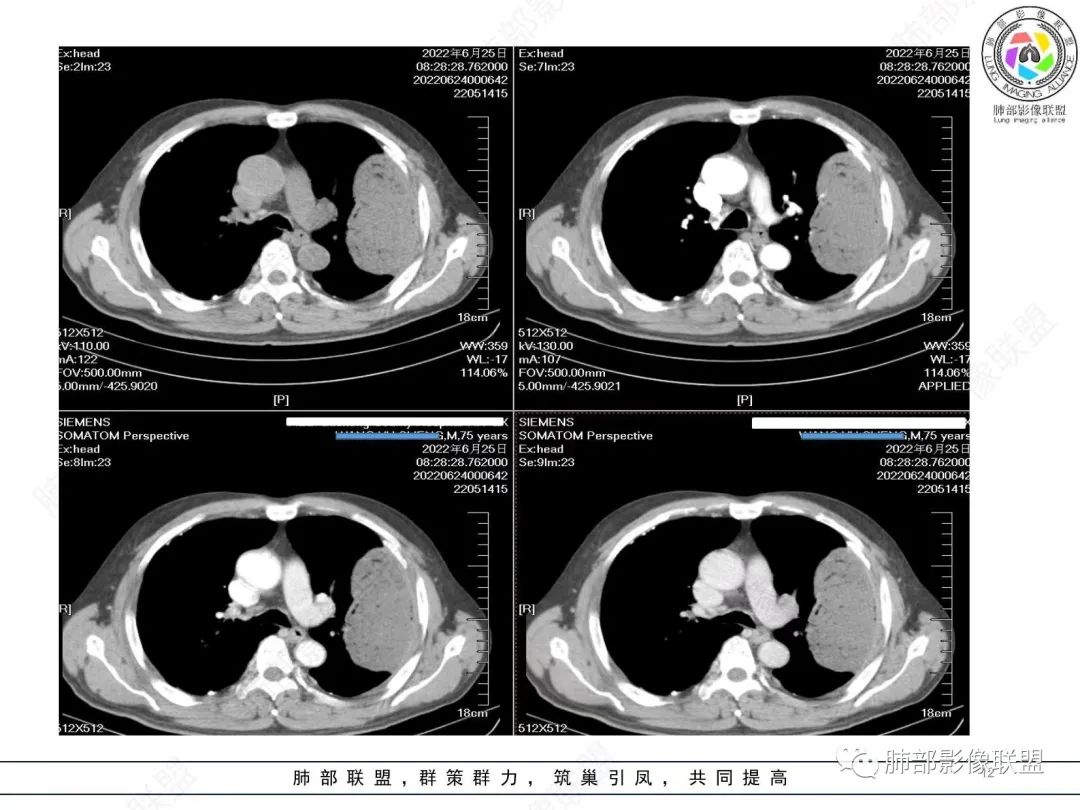

我再建一下血管。支气管进入,但是近端推移,堵塞

大肿块,边缘光滑,深分叶

近端支气管堵塞、推移为主

部分类似于脐凹征

内部支气管扩张

肺动脉推移为主,边缘部分进入

淋巴瘤符合吗?

淋巴瘤肯定不符合了。

仅仅只有血管漂浮和支扩支持淋巴瘤。其他细节都是否定淋巴瘤的。

大肿块、表面光滑但深分叶,肺门侧支气管堵塞

我一开始诊断恶性,定在淋巴瘤,还觉得信心满满

回头看,内部支气管近端其实不连续,伴随肺动脉不存在

这两点就不符合

还有如果从支气管的特点考虑黏膜相关性淋巴瘤,其整体应该是边缘不清楚为主,肺炎样为主。